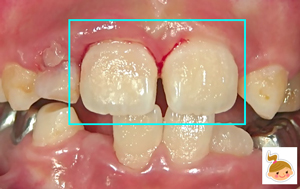

患者さんは、小学校4年生。主訴は「学校でこけて前歯をぶつけた。血が出てグラグラしている。唇も切れて腫れている」でした。 グラついて、出血している前歯2本は、大人の永久歯。そのお隣りの歯(乳歯)もグラついて抜けかけ。 前歯2本を固定するには、とても難しいケースでした。 口唇も腫れあがり視野の確保が易しくなかったため、矯正装置(保険治療)を利用して、短時間での強固定を試みました。1ヶ月間、このままの状態で経過をみる予定です。 泣かずによくがんばりました◎えらかったよ!